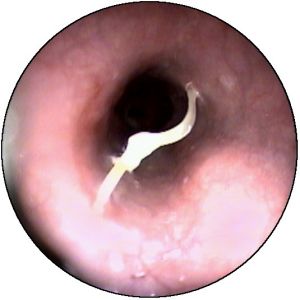

胃息肉胃息肉很少有陽性體徵,合併炎症時上腹部可有壓痛,出血多者有繼發性貧血表現。X線胃鋇餐透視和胃鏡檢查是診斷胃息肉的主要方法。X線胃鋇餐透視顯示胃腔內呈現圓形或半圓形邊界整齊清晰,表面平整的充盈缺損,多數在1cm左右大小,有蒂者可見其移動。胃鏡檢查對診斷實屬必要,鏡下可見胃壁黏膜上有圓形或半圓形隆,一般小於2cm。邊界清晰,表面光滑平整,色澤呈正常黏膜象或呈鮮紅色,質地柔軟,有蒂或無蒂,單發或多發。部分息肉呈菜花狀表現,其表面或有糜爛或有潰瘍。菜花狀息肉和體積大於2cm者有惡變之可能,活組織病理檢查有助於鑑別診斷。